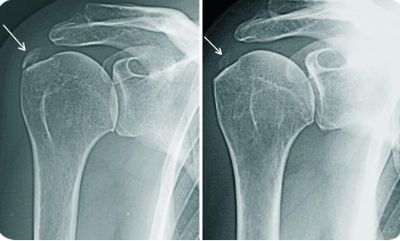

- рентгенографию в двух проекциях;

- рентгенография;

Основным методом диагностики является рентгенографическое исследование позвоночного столба.

Для диагностики применяются рентгенография, МРТ и КТ.

Диагностика искривления позвоночника включает осмотр пациента и рентгенографическое исследование.

Диагностика включает осмотр, пальпацию и рентгенографию.

Для диагностики проводят рентгенографию, иногда используют МРТ или КТ.